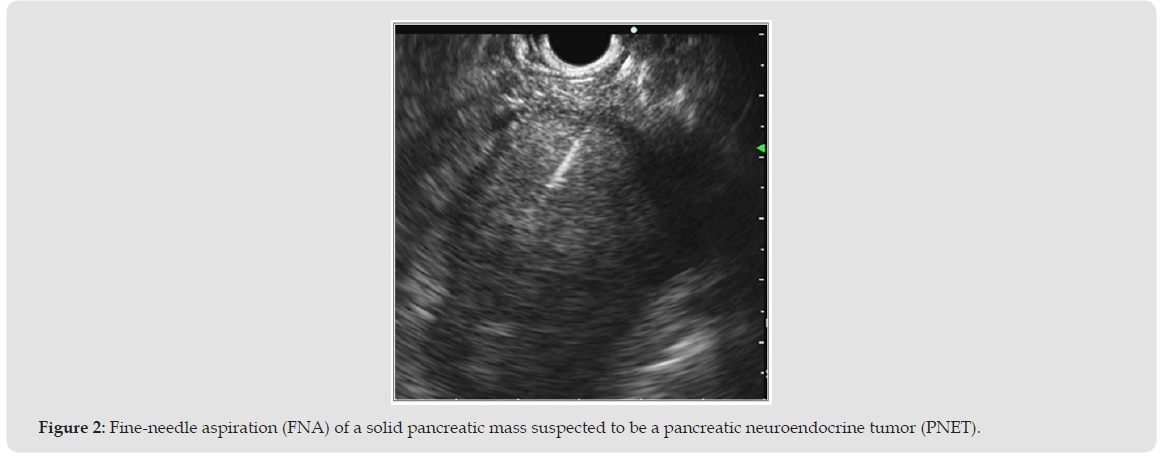

EUS remains highly accurate in differentiating T1 from T2 esophageal cancer [1] and in guiding neoadjuvant therapy for rectal cancer [2]. For pancreatic adenocarcinoma, EUS detects small lesions often missed by CT, with pooled sensitivities around 95% and specificities >90% [3,4]. Meta-analyses confirm that FNB outperforms FNA in sample adequacy and diagnostic accuracy [5,6]. EUS-FNB also allows immunohistochemistry and Ki-67 index assessment in pancreatic neuroendocrine tumors (PNETs), achieving concordance >85% with surgical specimens [19]. For pancreatic cystic neoplasms, EUS identifies mural nodules, septa, and ductal communication [7,8]. Fluid aspiration for CEA and cytology, and increasingly molecular analysis, improves differentiation between mucinous and non-mucinous cysts [7,8]. Contrast-enhanced EUS (CE-EUS) and elastography further enhance lesion characterization [16], while AI-assisted CH-EUS systems are emerging [17,18] (Figure 2).